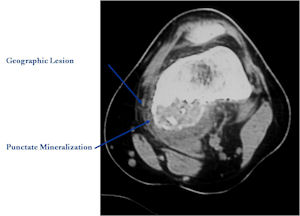

CT Scan:

- More useful for detecting mineralization and evaluating extent of bone destruction than plain X-ray

MRI:

- Also useful in determining extent

- There is often extensive edema around the tumor in the surrounding bone and soft tissues that can lead to a misdiagnosis of a malignant tumor.

- Soft tissue component usually surrounded by shell of reactive bone or periosteum (Egg Shell Rim of Calcification)